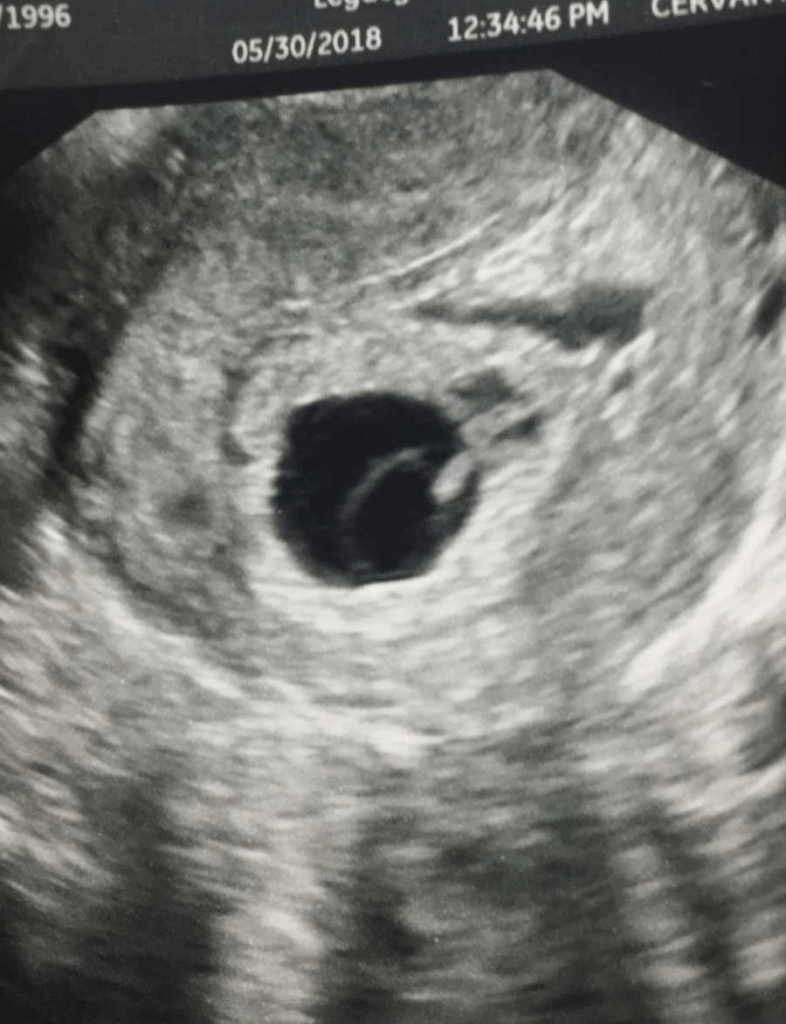

She made the first doctor’s appointment at around five weeks, the usual bloodwork, the ultrasound to confirm things were progressing. She and her husband walked into the exam room that day nervous but giddy. Then came words no parent ever wants to hear: “There’s nothing there.” The doctor called it a blighted ovum. A sac had formed but no baby inside, she explained. Berkley stared at the screen, trying to make sense of how she could be pregnant without actually having a baby. Shock, confusion, grief, all piled up in the same instant. Her husband held her hand while the doctor talked about taking medication to “help things pass.”

Back to the ultrasound table she went, her heart pounding this time for a different reason. Fear and hope clashed in her chest. Maybe it was a twin, maybe an ectopic pregnancy, maybe something else entirely. The transvaginal ultrasound revealed what the first one had missed. There was a baby. About six weeks along. But there was no heartbeat.